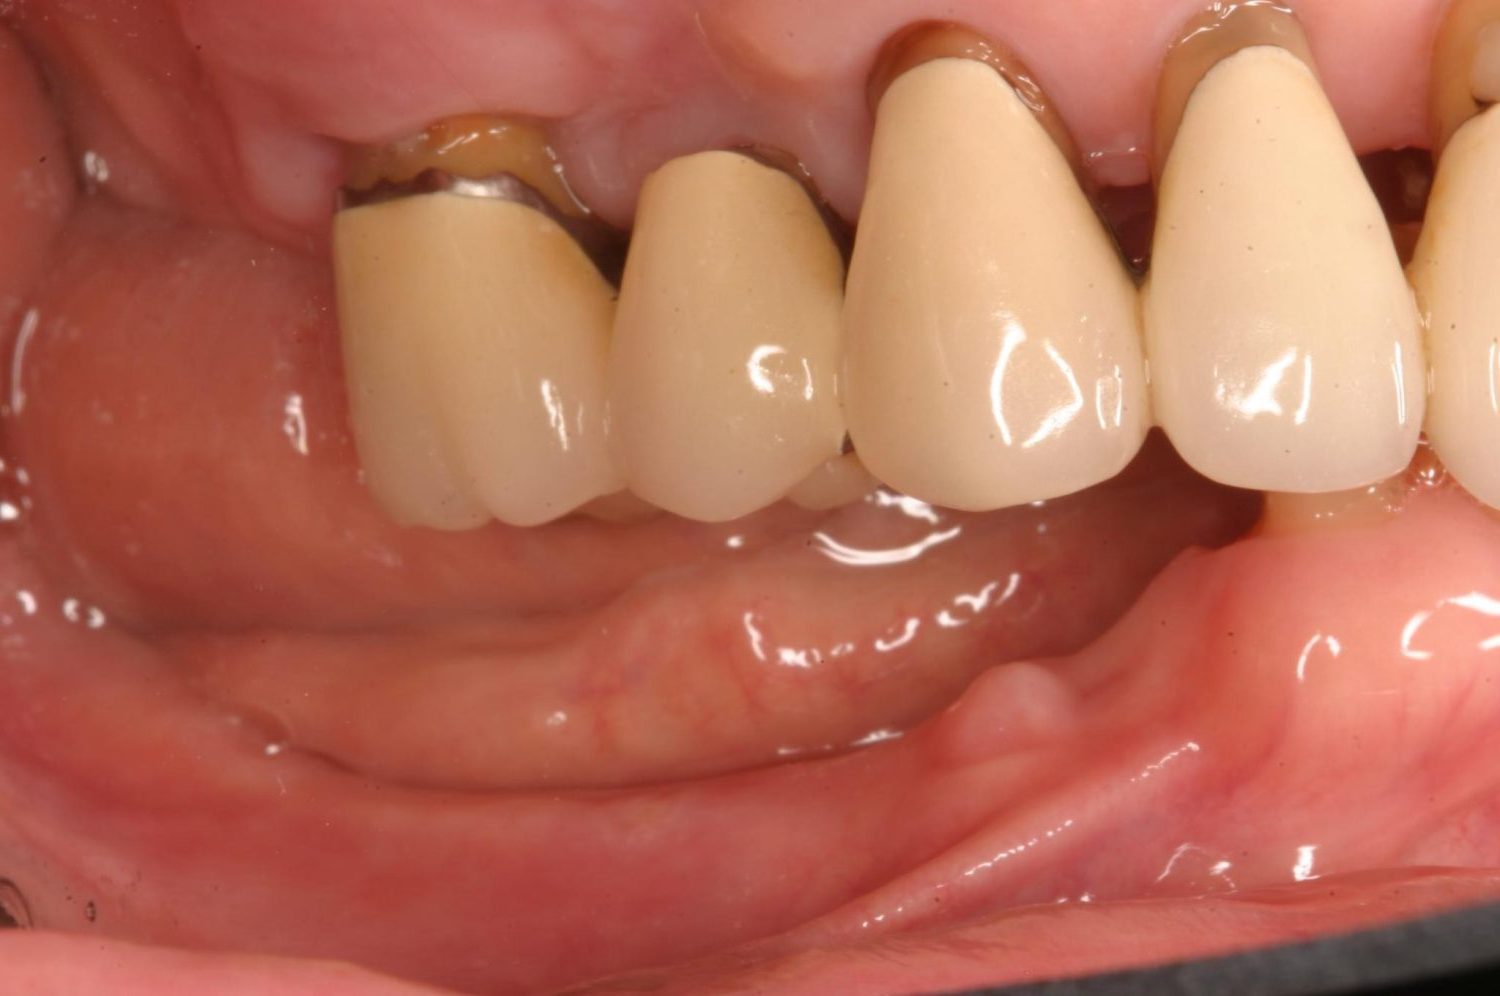

インプラント治療の症例紹介②

Before

After

主訴

前歯の脱落、歯肉の腫れ

治療内容

修復物の脱落時に支台築造のポスト部で歯質を破折。抜歯即時インプラント埋入をおこなったケース。

治療費

473,000 円(税込)

治療期間

8か月

治療回数

12回

想定されたリスク

※経年的な歯肉退縮の恐れ、インプラント周囲炎の恐れがありました。

残存した歯根に感染が少なく、抜歯時即時にインプラント埋入手術を行った。術後〇年経過し安定している状態。